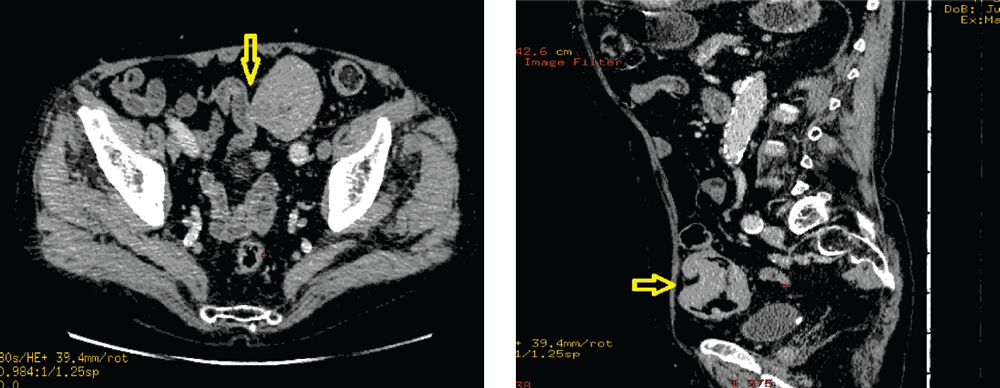

В оценке инвазии опухоли в соседние органы и ткани, поражении регионарных лимфатических узлов большое значение имела перфузионная спиральная компьютерная томография (рис. 4).

Рис. 4. Перфузионная СКТ. Признаки инвазии опухоли сигмовидной кишки в петлю тонкой кишки, поражение регионарных лимфатических узлов

Fig. 4. Perfusion CKT: signs of sigmoid tumor invasion in the small intestine loop, regional lymph node involvement